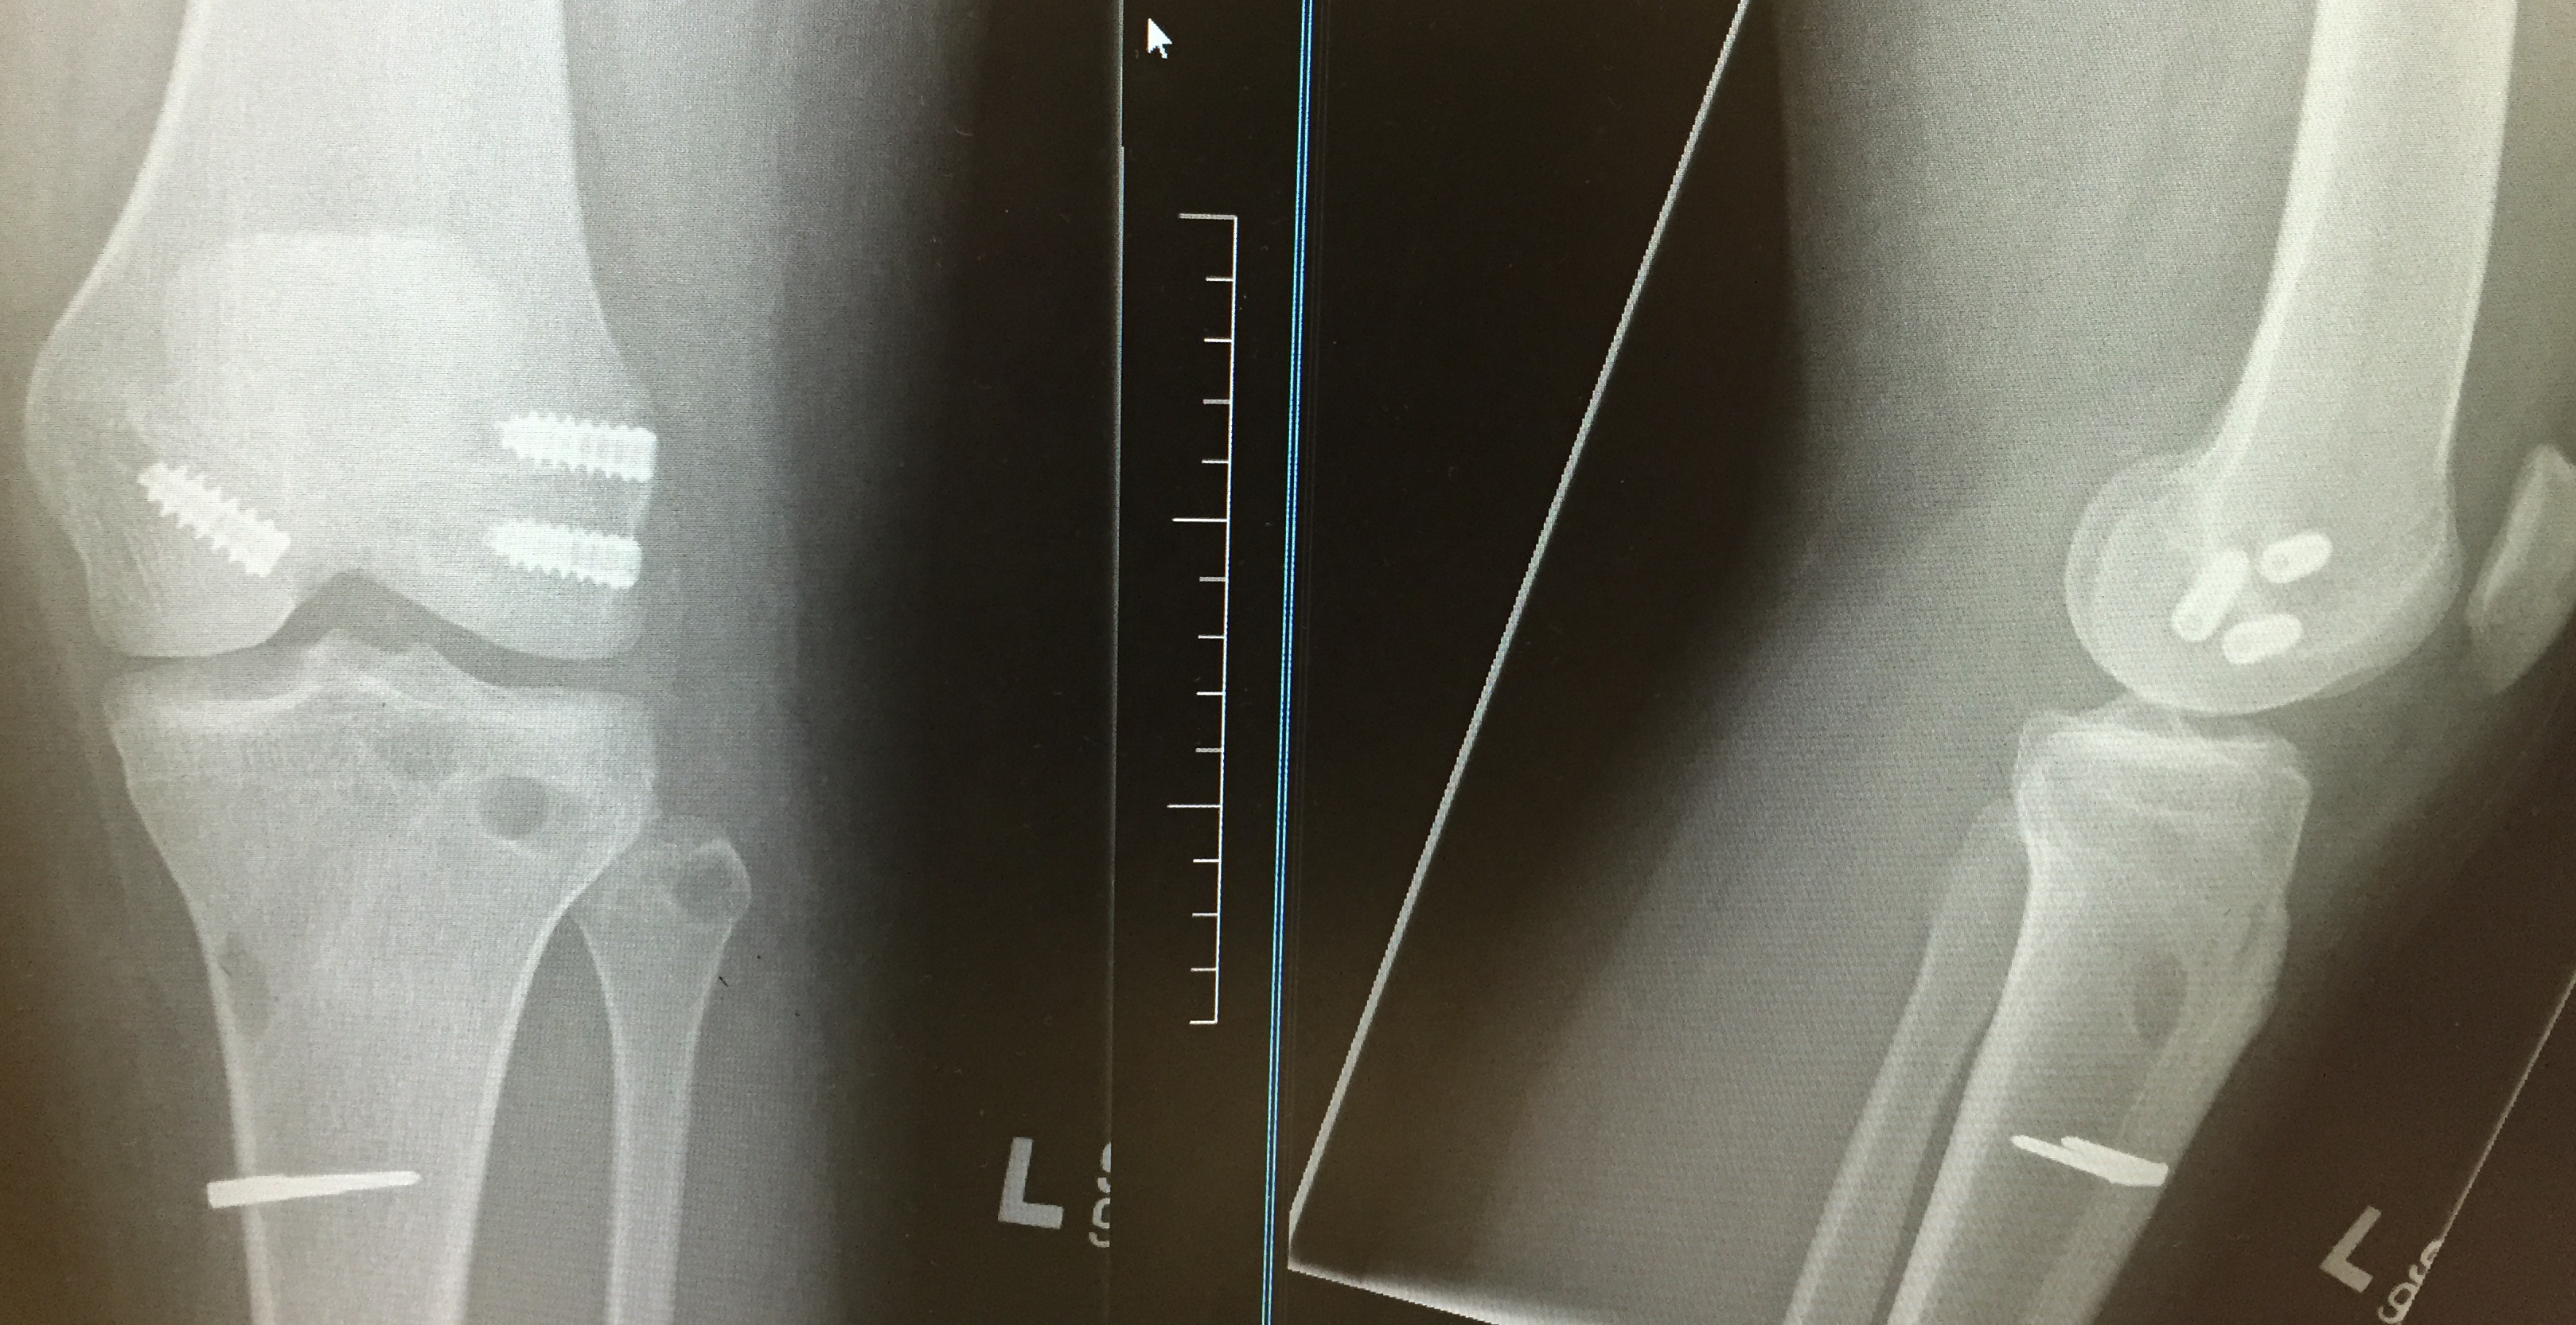

After 6 – 12 weeks, consideration of surgery can begin. An xray of both legs is important, to ensure that there is normal leg alignment. As a general rule, the ACL is reconstructed with the patella or hamstring tendon, and any significant PCL injuries reconstructed with tendoachilles allograft. Open surgery using tendoachilles allograft is required to reconstruct the LCL, on the outside of the knee.